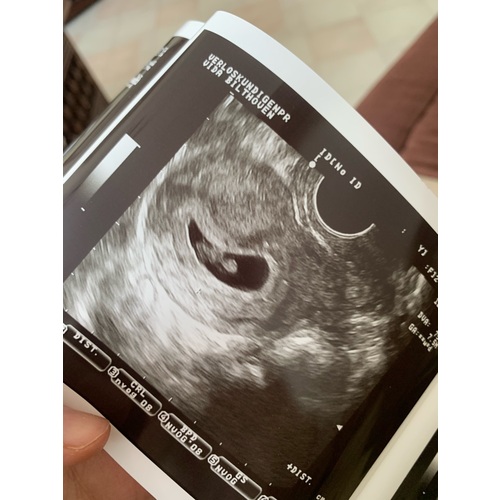

Inwendige echo: Zie je op de uitdraai van een inwendige echo de lichte vlek rechts in de baarmoeder? Dan verwacht je volgens de Ramzi-theorie een jongen. Wanneer je hem links in de baarmoeder ziet, zou je van een meisje in verwachting zijn.

Uitwendige echo: Als de echo via je buik is gemaakt, is de echo gespiegeld. Zie je op de uitdraai van de echo de lichte vlek rechts? Dan zou dit betekenen dat je een meisje krijgt. Een lichte vlek aan de linkerkant wijst bij een uitwendige echo op een jongen.

Oke dan ben ik heel erg benieuwd wat dit dan eventueel kan zijn volgens de ramzi methode dit is een inwendige echo geweest bij 8 weken zwangerschap